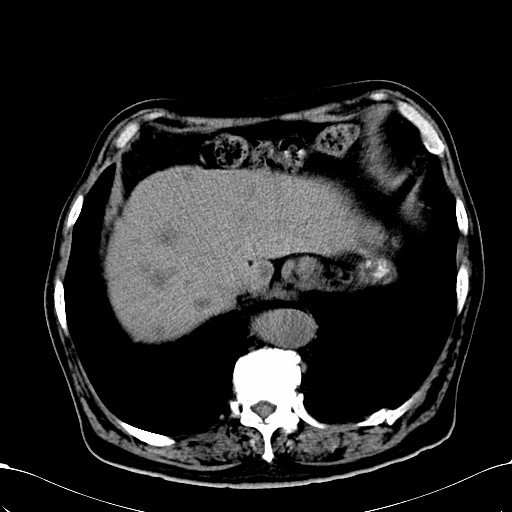

标题: CT28270:胰管扩张,肝多发占位 [打印本页]

标题: CT28270:胰管扩张,肝多发占位

患者,男,75岁。

肝脏多方低密度结节,边缘模糊,考虑多发转移,胰管明显扩张,建议增强扫描钩突情况

肝脏多发低密度灶,胰头似呈低密度,胰管扩张,建议增强,